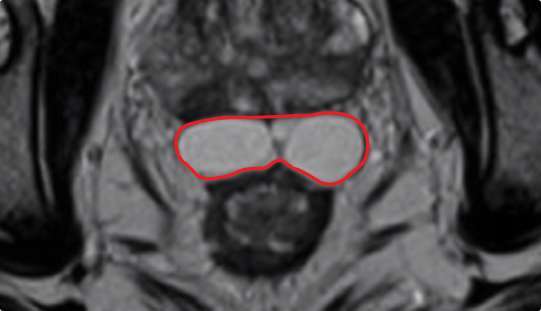

How hydrogel rectal spacer material impacts symmetrical implant placement

Symmetrical rectal spacer placement is important in order to offer complete coverage of the rectum during prostate radiation. Barrigel hydrogel spacer is the only sculptable spacer available. Due to its customization properties, it has been shown to achieve symmetrical placement >95% of the time.1 As a result of the quick polymerization of PEG Hydrogels, symmetrical placement is less achievable. In the PEG Hydrogel FDA clinical trial, symmetrical placement was achieved 49% of the time.2

Implant Symmetry RESULTS1

>95%